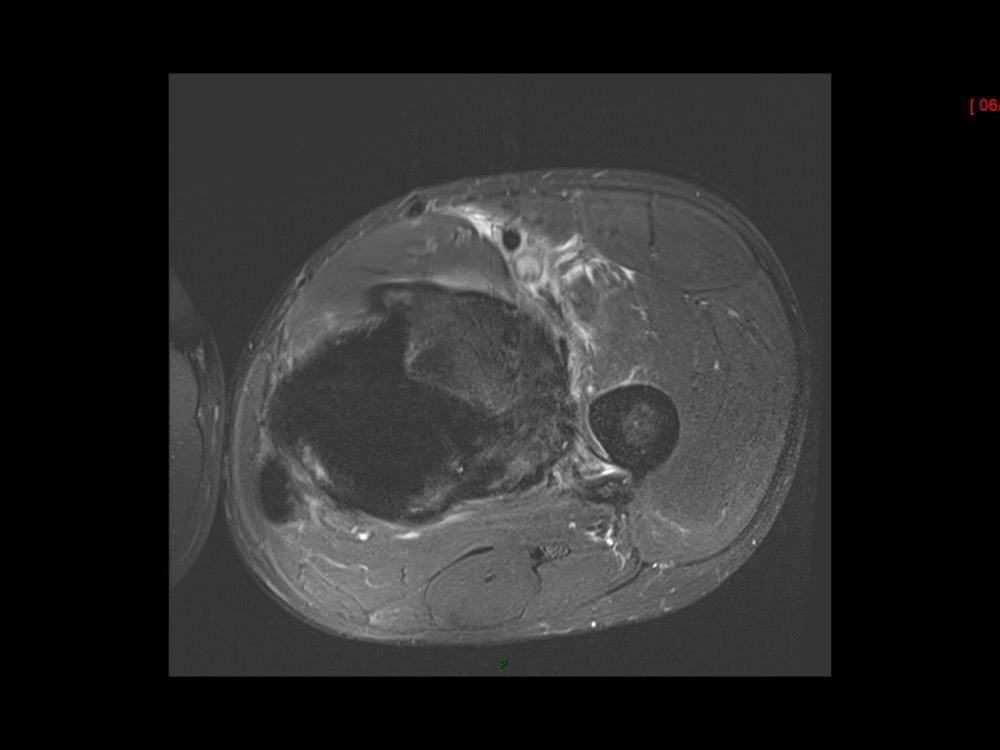

Moalla / Mihoubi-Bouvier / Drapé 18/05/2022